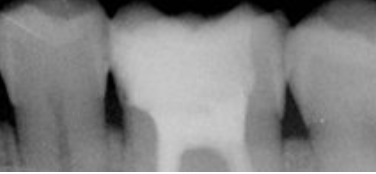

FICHE CLINIQUE Prothèse fixée conventionnelle : Couronnes et bridges